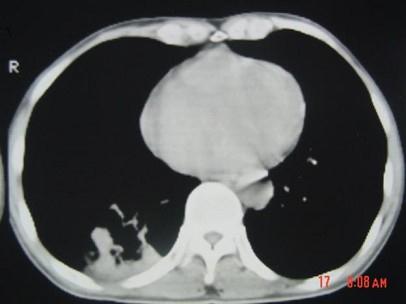

问题 男,40岁,胸背疼痛一周,消瘦一月,CT检查如图,最可能的诊断为 ( )

选项 A、右下肺肺泡癌 B、右下肺炎性假瘤 C、右下肺脓肿 D、右下肺炎 E、右下肺结核

答案 A